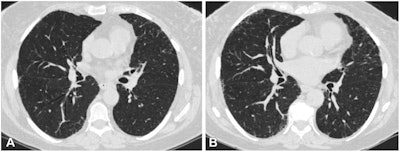

Axial chest CT scans (0.75-mm section thickness, reconstructed with b31f kernel) at (A) visit 1 and (B) visit 2 at the level of the takeoff of the right middle bronchus of a participant with 1.2 annual percentage quantitative interstitial abnormality progression. The female participant was 62 years old at [baseline] visit 1 and 67 years old at [follow-up] and a current smoker at both visits, with a 47.5 pack-year history at [follow-up]. This participant had four subsequent acute respiratory disease (ARD) events and three subsequent severe ARD events. Images and caption courtesy of the RSNA.